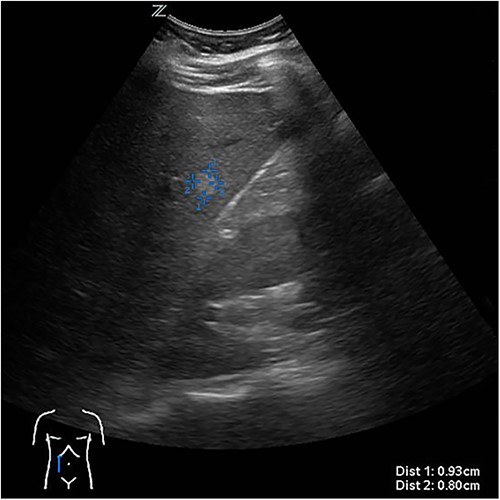

The presenting patient was a 40-year-old Brazilian native who had lived in Europe for ~26 years. Initially, the patient presented to her general practitioner with upper right quadrant pain. An ultrasound study (Fig. 1) showed a small hyperechoic lesion in segment VII measuring ~0.8 × 0.9 cm. Follow-up studies showed an expanding lesion with newer hyperechoic portions. In 2020 a liver specific magnetic resonance imaging (MRI) (Fig. 2) was performed. Here, again, the cyst was expanding, septated and had reached a size of 7.3 × 6 × 6.5 cm. A Echinococcus infection was considered, however, repetitive EIisa for Echinococcus sp./IgG was negative. The alpha protein was 2 ug/L, and well within normal limits. Due to increasing discomfort, an upper gastrointestinal tract endoscopy was performed. Here, gastritis and gastro-intestinal neoplasia could be excluded.

First documentation of liver cyst of the patient in ultrasound.